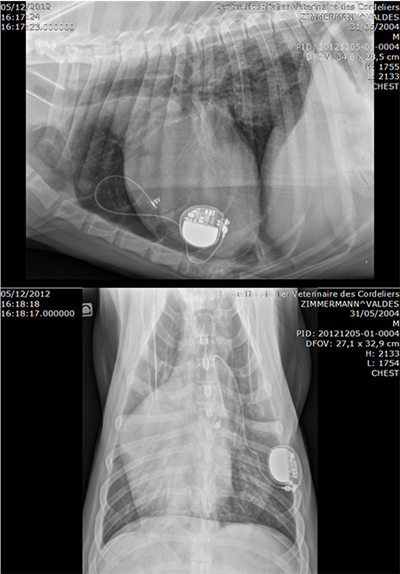

- Pulse generator : VVIR Medtronic ADAPTA ADSR 01

- Surgical time

- 46’ and 43 ‘ in Group 1

- 44’ and 22’ in Group 2

- Outcomes

- Hospital discharge 3 and 4 days PO in group 1 1 and 2 days PO in group 2